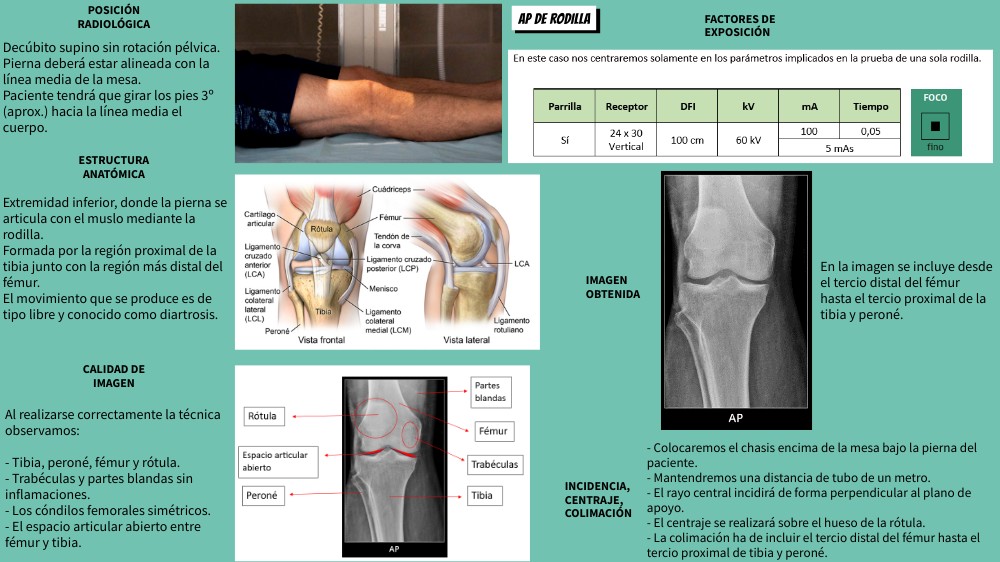

AP DE RODILLA

FACTORES DE EXPOSICIÓN

Decúbito supino sin rotación pélvica. Pierna deberá estar alineada con la línea media de la mesa. Paciente tendrá que girar los pies 3º (aprox.) hacia la línea media el cuerpo.

ESTRUCTURA ANATÓMICA

Extremidad inferior, donde la pierna se articula con el muslo mediante la rodilla. Formada por la región proximal de la tibia junto con la región más distal del fémur. El movimiento que se produce es de tipo libre y conocido como diartrosis.

En la imagen se incluye desde el tercio distal del fémur hasta el tercio proximal de la tibia y peroné.

IMAGEN OBTENIDA

CALIDAD DE IMAGEN

Al realizarse correctamente la técnica observamos: - Tibia, peroné, fémur y rótula. - Trabéculas y partes blandas sin inflamaciones. - Los cóndilos femorales simétricos. - El espacio articular abierto entre fémur y tibia.

- Colocaremos el chasis encima de la mesa bajo la pierna del paciente.- Mantendremos una distancia de tubo de un metro. - El rayo central incidirá de forma perpendicular al plano de apoyo. - El centraje se realizará sobre el hueso de la rótula. - La colimación ha de incluir el tercio distal del fémur hasta el tercio proximal de tibia y peroné.

INCIDENCIA, CENTRAJE, COLIMACIÓN